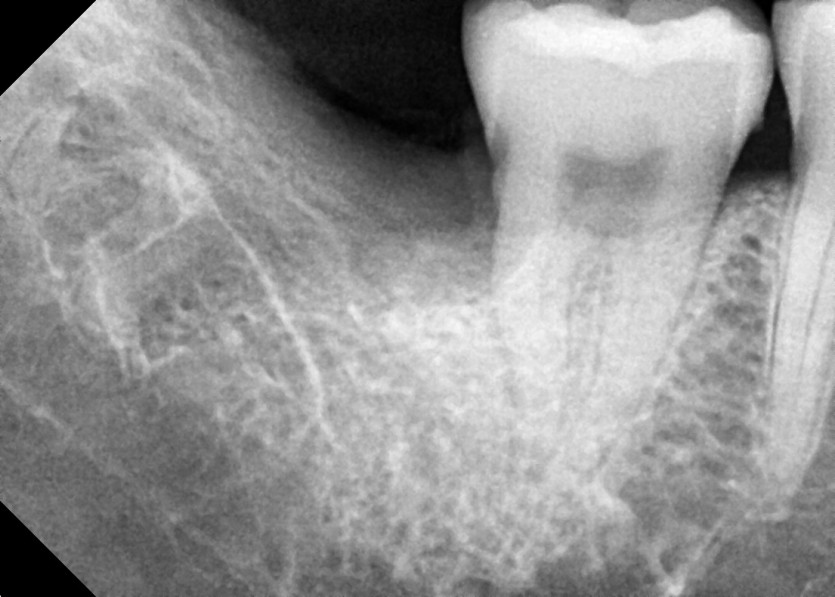

#18,48 사랑니 발치

구강 외과 전문의가 당일 발치했습니다.